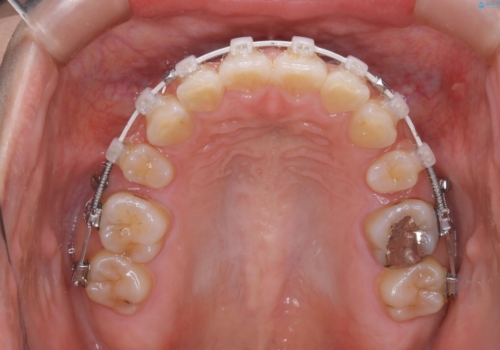

- 矯正装置

- 審美装置(ワイヤー)

- 前歯のがたつきが気になるとご相談にいらした方です。当初は前歯の部分矯正をご希望されていましたが、全体的に整えることで審美的、機能的な歯並びとなりました。

当初は上顎前歯のみの部分矯正をご希望されていましたが、部分的に前歯のみを並べると出っ歯感がつよくなり、食事もしづらくなる可能性をお伝えしました。全顎的な矯正治療により、審美的、機能的な歯並びとなりました。